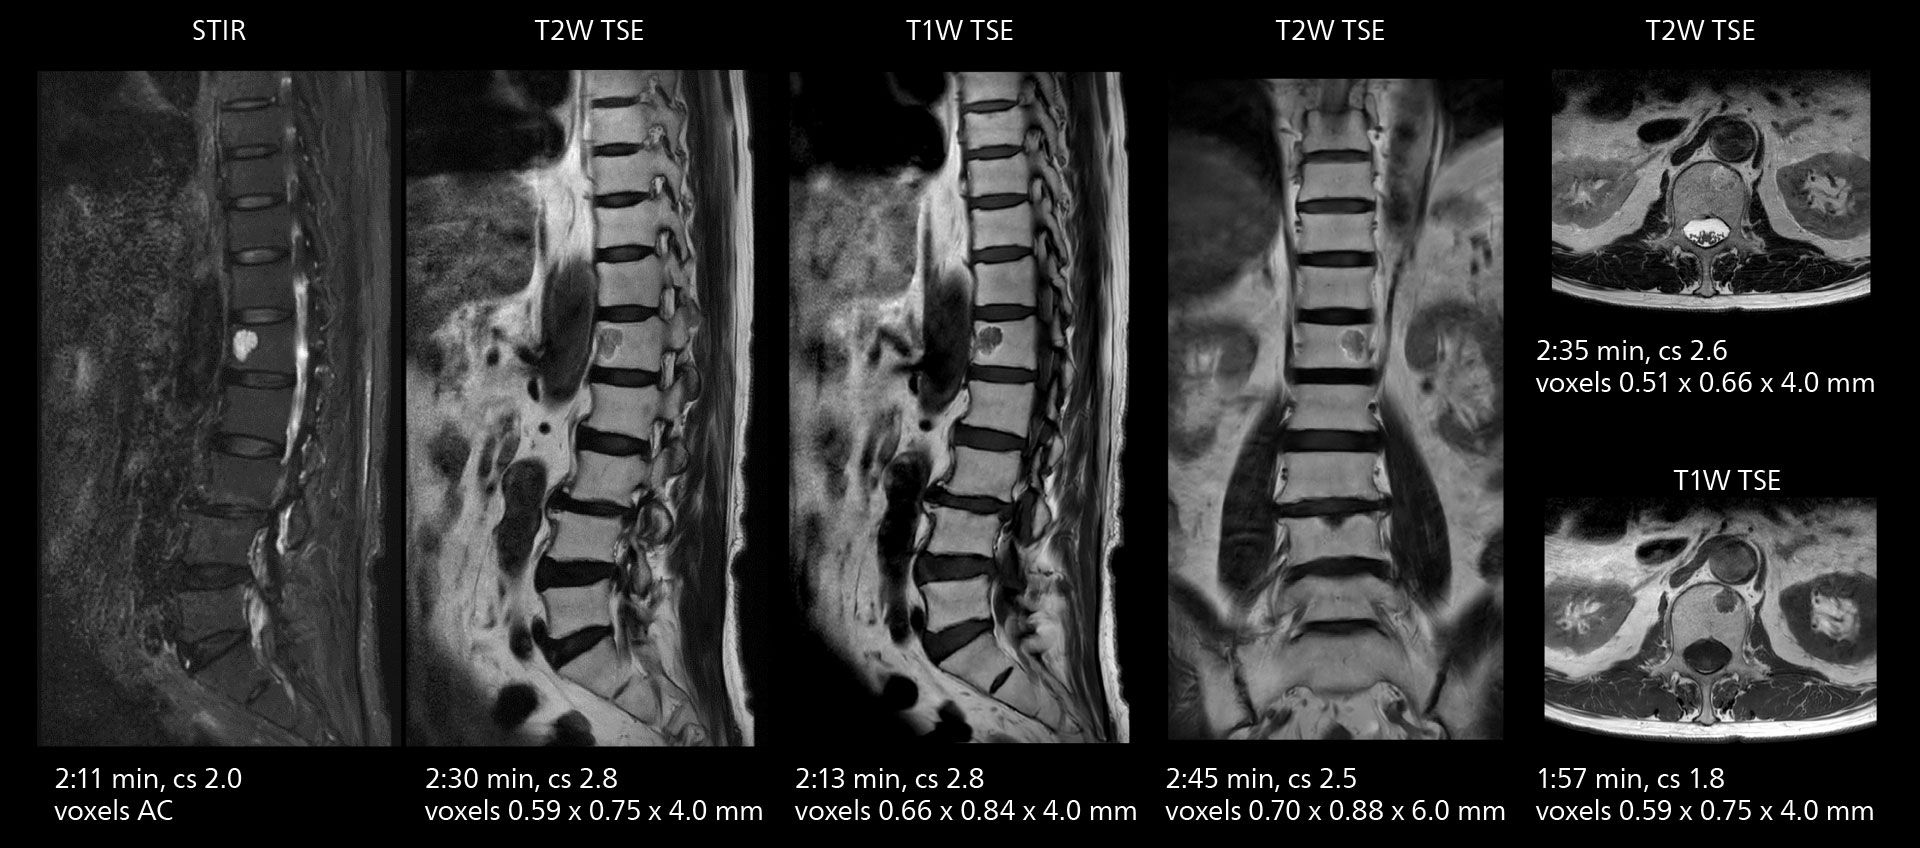

Lumbar spine MRI

Crisp images are obtained with high resolution and short scan times using Elition X. A cyst can be seen.

Lumbar spine MRI

Crisp images are obtained with high resolution and short scan times using Elition X. A cyst can be seen.